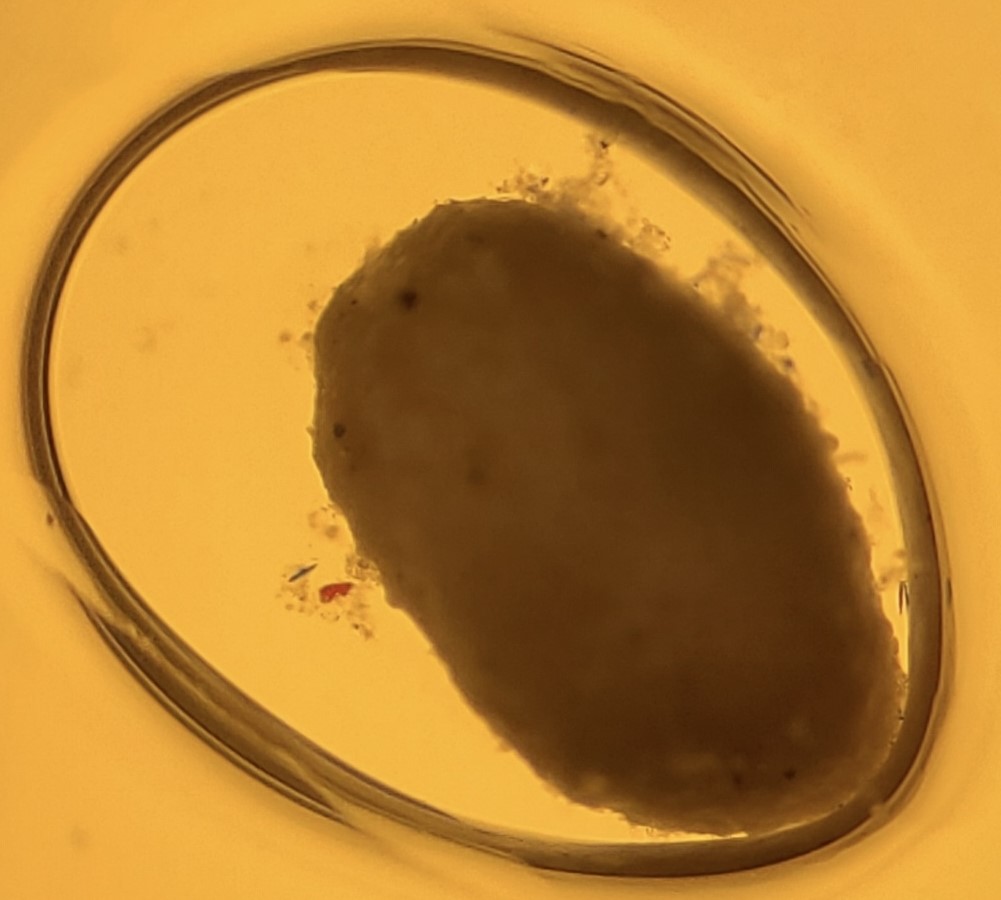

Picture 1 & 2

The first Bicolor Angelfish (Picture 1) was originally in the medication of Chloroquine Phosphate and Methylene Blue for Ich, but this medication was not working and the small dot in the blue/black region at the end of the fish near the caudal fin circled in red is a fluke. The flukes could have come from the wholesaler the Bicolor Angel (Picture 1) came from, or it could have come from the other fish that were in the tank with the Angelfish (Picture 1). Less than a week after the fish arrived at our store, the fish had a fluke attached to it. After this observation, the quarantine team netted the fish, and gave it a freshwater dip. In this picture, the Angelfish (Picture 1) was placed in a small bucket with freshwater, and some flukes did come off. The quarantine team sampled what came off the fish, and placed it on a slide under the microscope (Picture 2). The other fish in with the Bicolor Angelfish (Picture 1) were moved to a different tank to prevent the spread of the flukes. The Bicolor (Picture 1) was placed in a new, clean tank with Prazipro, which is a medication to treat flukes and other worms. The Angelfish (Picture 1) got another freshwater dip three days later, and started to develop a dark color on its face and passed away. The cause of the dark color appearing on its face is unknown, but because of the holes the flukes had made on the skin of the Bicolor Angel (Picture 1), it is likely that the fish developed a bacterial infection, which would explain the dark patches on the fish’s face.